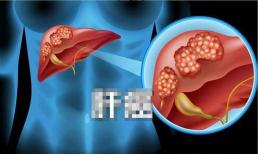

Vì sao ung thư gan ngày càng nhiều? Bác sĩ: 1 loại trái cây hại gan hơn cả uống rượu

Chăm sóc sức khỏe - 30.01.2023

Gan là cơ quan “câm”, dù có khó chịu cũng không phát ra tín hiệu đau nên bệnh gan dễ bị bỏ qua ở giai...

Từ xơ gan đến ung thư gan, cơ thể sẽ sinh ra '3 cơ hội', nếu phát hiện kịp thời thì có thể chẩn đoán và điều trị sớm

Chăm sóc sức khỏe - 19.04.2022

Gan là cơ quan tiêu hóa quan trọng của cơ thể con người, nó có thể tổng hợp được nhiều chất dinh dưỡng quan trọng...